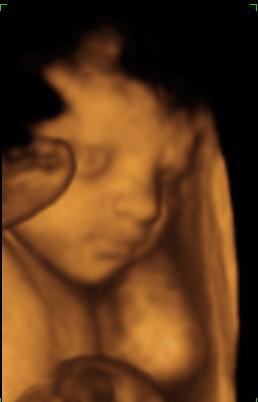

A második képen nyitva van a szeme is